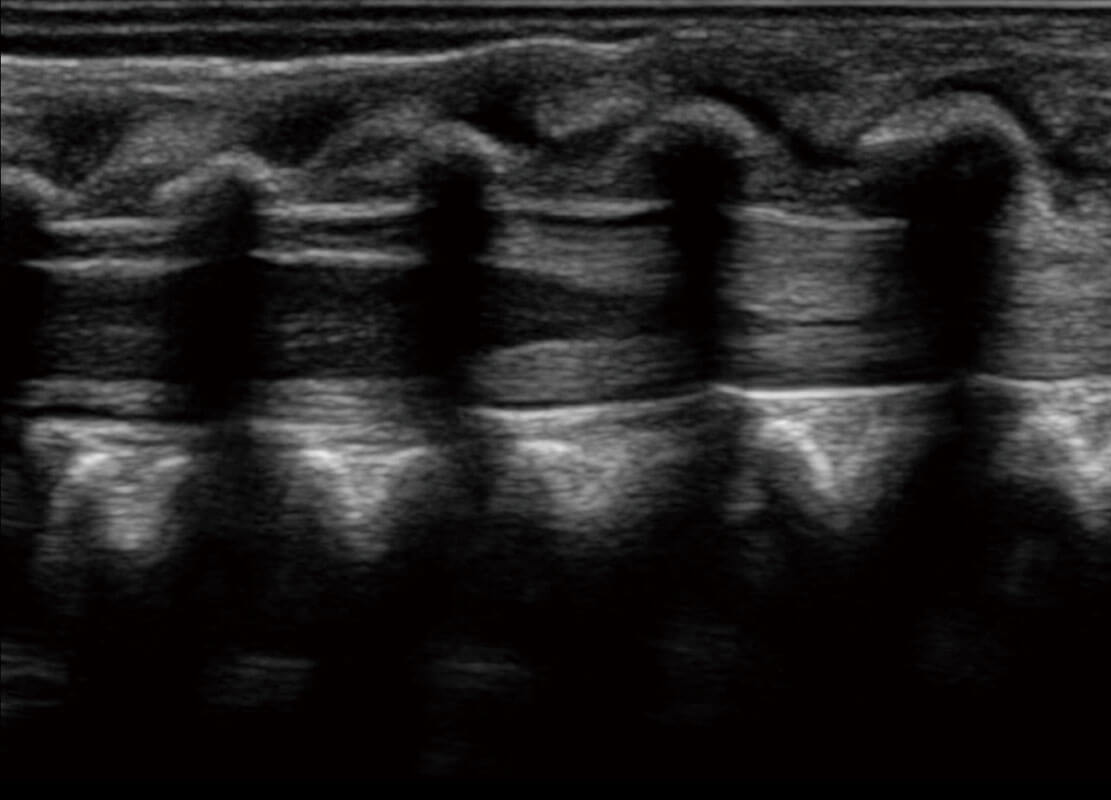

早孕-胎心

高分辨率容积成像-早孕胎儿

胎儿体循环

光影成像-孕囊